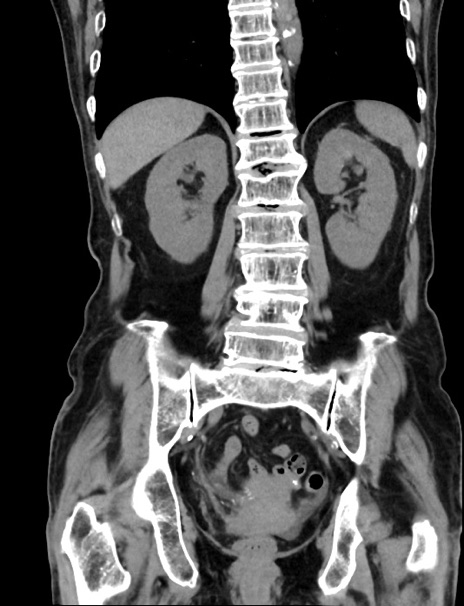

症例33(冠状断像)

【症例】70歳代 女性

【主訴】心窩部痛

【現病歴】延髄病変の精査・加療にて神経内科入院中。本日より心窩部痛あり。

【身体所見】右下腹部を中心に圧痛と反跳痛あり。

【データ】WBC 10900、CRP 0.02